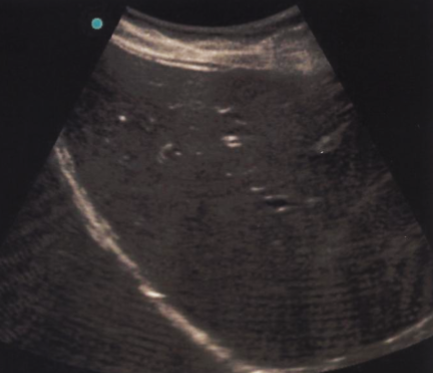

In the image, we see horizontal lines traveling through the image, especially at the bottom (far field)